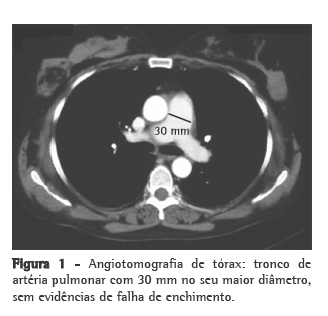

O ecocardiograma mostrou insuficiência tricúspide importante e pressão sistólica de artéria pulmonar estimada em 75 mmHg, sem sinais de disfunção sistólica ou diastólica do ventrículo esquerdo. A eletroneuromiografia foi compatível com polineuropatia desmielinizante sensitivo-motora crônica com envolvimento axonal secundário. A dosagem de hormônios tireoidianos revelou hipotireoidismo subclínico. A imunofixação de proteínas urinárias apresentava aumento monoclonal de IgA, com aumento de kappa. A investigação de doença tromboembólica resultou negativa; a angiotomografia de tórax evidenciou tronco de artéria pulmonar com 30 mm de diâmetro no seu maior aumento, sem falhas de enchimento (Figura 1).